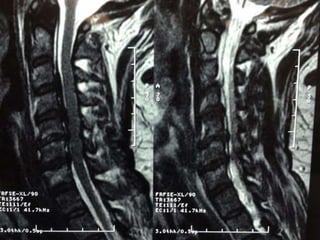

48 year old man with right fifth finger pain and numbess

S/P C7T1

ACDF

persistent

symptoms of

ataxia, neck

pain, fine

motor hand

dysfunction

48 year oldman with right fifth finger pain and numbess

persistent symptoms of ataxia, neck pain,fine motor hand dysfunction